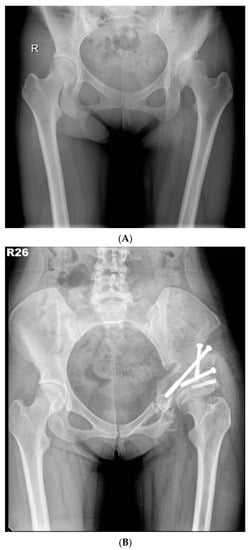

In 2012, we proposed a modified approach for triple innominate osteotomy [8] with the advantage of more favourable femoral-head medialisation and coverage when compared with the traditional approach. In this study, the modified approach was implemented as follows (Figure 2A,B).

Figure 2.

(A) Preoperative anteroposterior standing radiograph of a 26-year-old woman who underwent MTI osteotomy for symptomatic left hip dysplasia. (B) Postoperative anteroposterior standing radiograph showed good coverage of the femoral head.